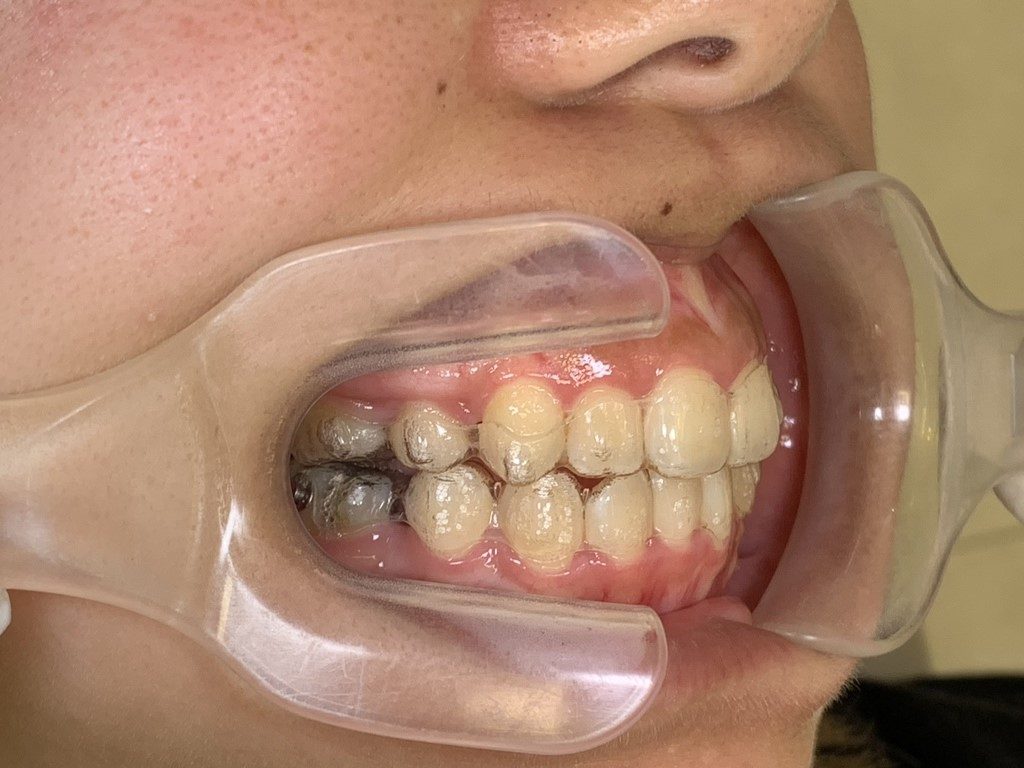

↑全く「浮き」がない状態です。

このようにしっかりとチューイーを毎回使用し、全ての部位を「浮き」がなくマウスピースをフィットさせることが重要です☆